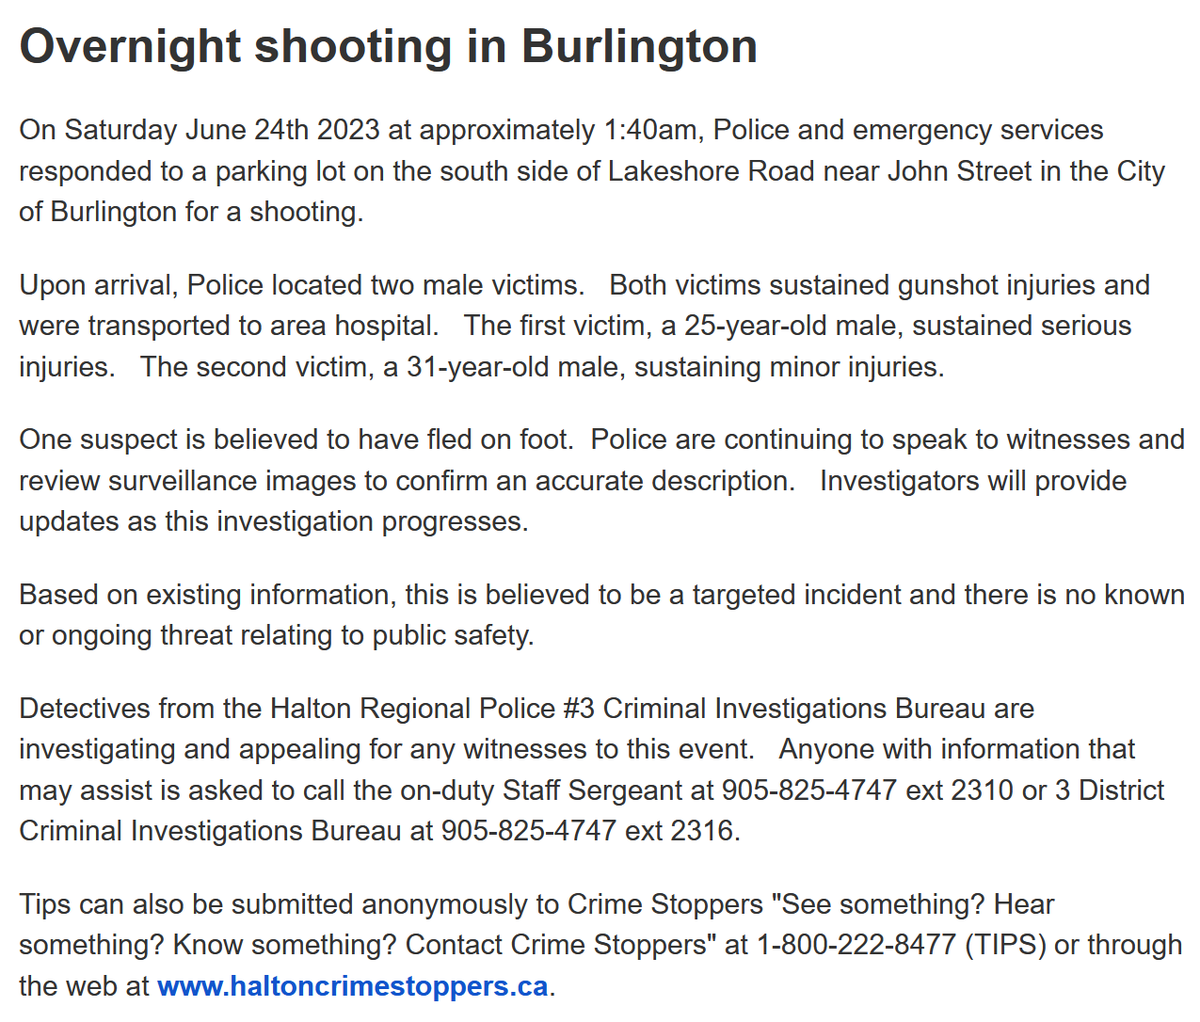

DR on Twitter: “.@HaltonPolice investigating a double shooting in the …

GUNSHOT WOUND TO CHEST | Buyxraysonline

Cureus | Gunshot Wound to the Chest With Retained Epicardial Bullet

Thoracic gunshot wound | Radiology Case | Radiopaedia.org